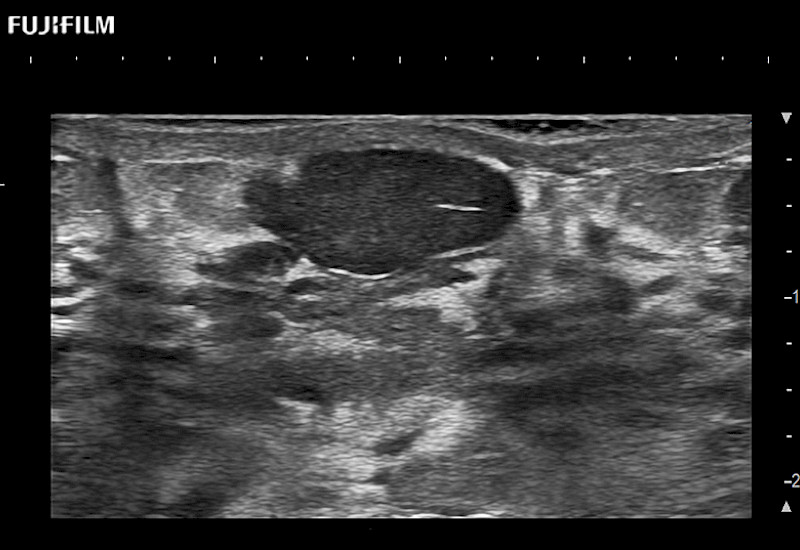

The ARIETTA 750 incorporates all of the proven technologies and functions that medical professionals have come to expect from Fujifilm Healthcare.

ARIETTA 750 is the definitive diagnostic ultrasound solution for any clinical setting - Private Office, Imaging Center, or Hospital. The ARIETTA platform provides the ultimate in clinical performance with its state-of-the-art features and large user-friendly display.

The ARIETTA 650 DI combines trusted Fujifilm Healthcare technologies and features tailored for surgical oncology.

Designed to meet the demands of surgeons, the ARIETTA 650 DI offers precise guidance. Its advanced capabilities and large, intuitive display offer accurate and efficient care in operating rooms and specialized surgical settings.